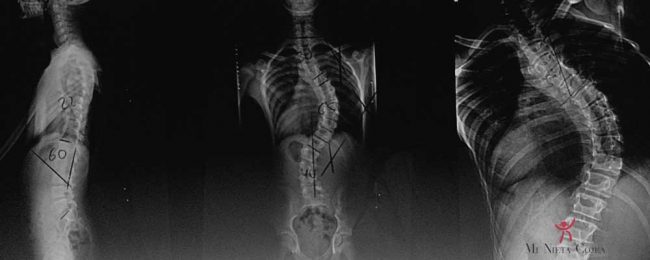

Escoliosis

Ni miedo ni vergüenza, tiene una mala fama creo que inmerecida. Como muchas otras cosas las hay malas y de las que “da igual” La escoliosis es una espalda torcida… sí, vale. Pero debe de haber algo más detrás de todo esto cuando hay traumatólogos que se dedican exclusivamente a esto. Para la escoliosis hablamos…